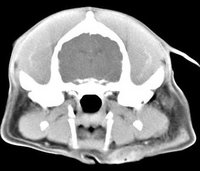

imágenes de TC en el perro | ||||||||||

ejemplo de imágenes de TC en el perro. Nótese la celulitis en la región parotídea izquierda | ||||||||||